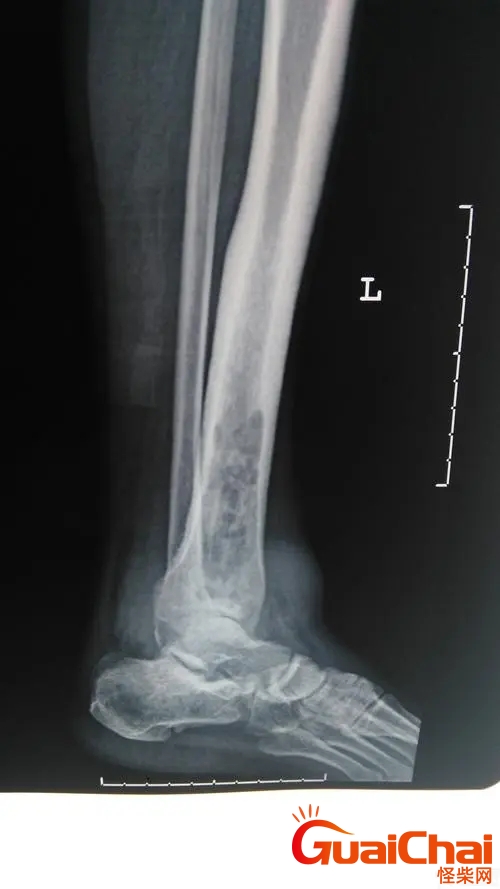

骨髓炎的症状表现?骨髓炎是什么病严重吗?骨髓炎为一种骨的感染和破坏,可由需氧或厌氧菌,分枝杆菌及真菌引起。骨髓炎好发于长骨,糖尿病患者的足部或由于外伤或手术引起的穿透性骨损伤部位。儿童最常见部位为血供良好的长骨,如胫骨或股骨的干骺端。

1.大约有33%的患者是因为外伤而导致的骨髓炎,比方说如果患者受到了刀伤,开放性的伤害,以及一些闭合性的伤害或者是在做关节的手术时操作没有经过严格的消毒,都有可能导致病原菌侵入到骨组织里面引起骨髓炎。

2.另外有51%的患者是因为血源性的感染而造成的骨髓炎,如果患者身体关节部位出现了一些化浓性的感染,那么细菌就会通过血液循环进入到骨骼的组织里面继而发生骨髓炎。

3.还有15%的患者是因为感染性的因素而造成的骨髓炎发生,比方说,如果患者的一些伤口化脓部位接近骨组织,那么炎症就会慢慢的侵蚀到骨髓,骨髓炎因此而产生。

另外,比较严重的化脓性细菌如果侵入到骨髓里面,那么就会造成骨髓腔的感染,患者往往出现炎症的反复发作,甚至有可能造成肌肉萎缩的严重后果。此时如果患者在发生一些骨折的现象,那么就容易造成肢体短缩或者是畸形,若是发病的区域接近关节部位,容易造成关节的挛缩甚至是僵硬。